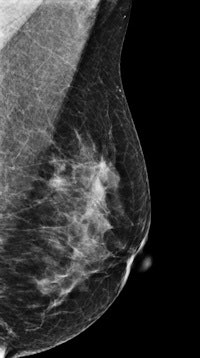

DBT has been gaining popularity with the publication of studies indicating that it has a higher cancer detection rate and lower recall rate compared with 2D mammography, particularly in women with dense breast tissue. But many of these studies have used two-view DBT protocols that acquire both mediolateral oblique (MLO) and craniocaudal (CC) views -- and this can create issues regarding radiation dose and length of reading time.

As an alternative, researchers have developed techniques that combine single-view DBT with single-view 2D mammography and have reported good performance for this combined protocol compared with two-view 2D digital mammography. But no study has reported on both diagnostic performance of the combined protocol and its radiation dose, according to Dr. Sung Ui Shin from the radiology department at Seoul National University Hospital and colleagues.

The combined technique used an MLO DBT view combined with a CC 2D digital mammography view. Three readers reviewed all studies and calculated their specificities and sensitivities. The data were also analyzed by breast thickness and density, while radiation dose for both techniques was represented by average glandular dose (AGD).